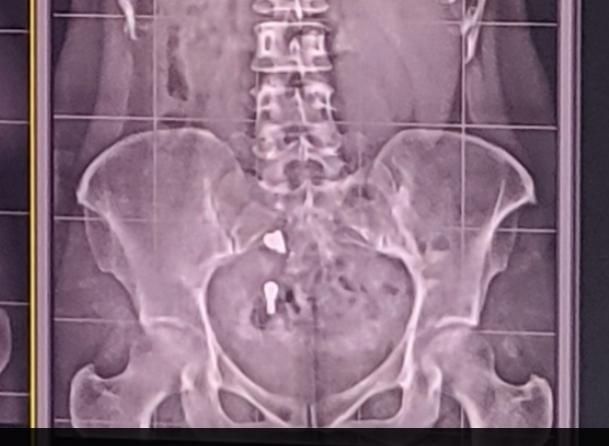

경추이상으로 상반신 엑스레이를 찍었는데 밑에보니까 결석같은게 보이는데 맞나요? 두개나있어요 (청바지입고 찍긴했습니다..)분석부탁드립니다

분석보다는 크기가 상당하시 때문에 일단 바지 주머니에 뭐가 들었는지 바지에는 특별히 장식이 있는지를

먼저 확인을 해보셔야 할 것 같습니다.